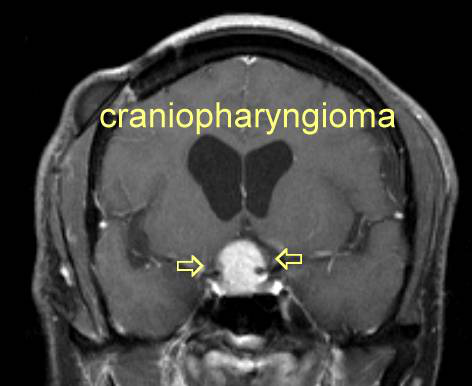

颅咽管瘤是一种良性肿瘤(肿瘤),来自于鞍区及其周围(鞍旁区域)的胚胎组织。蝶鞍区位于颅底的中央,主要包括垂体,人体的“主腺”和蝶鞍,颅骨中的骨性凹陷(特别是蝶骨)。相关阅读:INC德国Schroeder教授关于神经内镜经鼻入路治疗颅咽管瘤的解析

颅咽管瘤每年以每百万个人约0.5至2个趋势发展,并具有双峰分布,年龄为5至14岁,年龄为50至74岁。许多专家认为颅咽神经瘤是一种慢性疾病,因为即使通过外科手术完全切除(切除)它们也容易复发。肿瘤本身通常不是危险的,因为它是良性的,并且很少变成恶性的。但是,肿瘤的位置会压迫垂体并导致荷尔蒙功能障碍。视交叉,两个视神经部分交叉,位于垂体上方,因此可被颅咽管瘤压迫,导致视觉缺陷。与垂体相连的下丘脑也可能受损,是在手术后。由于下丘脑是许多生物学功能的调节剂,因此对该结构的损害与诸如肥胖症(下丘脑肥胖症)的发展和睡眠周期的损害有关。颅咽管瘤可压迫的另一解剖结构是脑室中的门罗孔。如果闭孔,则通常在大脑和脊髓中循环的脑脊液会积聚(一种称为脑积水的状况),可能导致多种症状,包括婴儿头增大。颅内压升高也可引起头痛和恶心。颅咽管瘤的治疗包括手术切除肿瘤和放射治疗,是当肿瘤由于其位置不能完全切除时。

颅咽管瘤患者较初可能会出现神经,视觉和激素功能障碍,可能需要神经科医生,眼科医生和内分泌科医生进行评估。然后将需要放射科医生或神经放射科医生来解释医学影像。临床表现,实验室价值和医学影像学的结合将导致颅咽管瘤的临床诊断。可以由神经病理学家确认诊断,一旦切除(切除)后将对其进行显微镜分析。